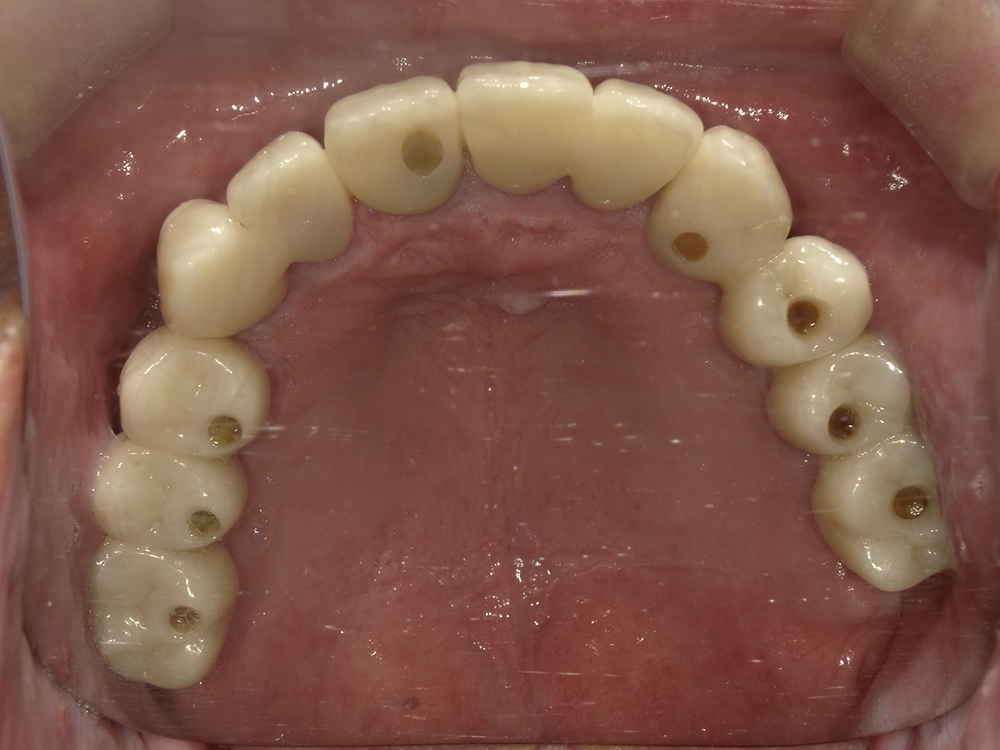

53歳 男性

- 主訴

- 全然噛めない。上の歯が取れてきた

- 処置内容

- 上顎:8本 下顎:2本

- 治療費用

- 上顎:約320万円(税込)、下顎:約160万円(税込)

- 治療期間

-

上顎:1年(仮歯まで8か月)

下顎:8か月(仮歯まで5か月)

- リスク

- 上部構造物、仮歯の破折、術後の腫れ(3日)、人工歯根脱落リスクがあります